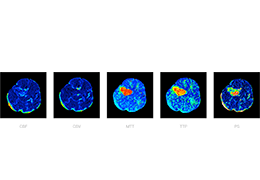

成像智能。

Eclipse 成像智能功能提供强大的处理能力和最佳质量的影像,同时减少质量错误并提高剂量效率。

凭借 AI、专有算法和先进的影像处理能力,提供出色的影像质量和无与伦比的诊断信心。